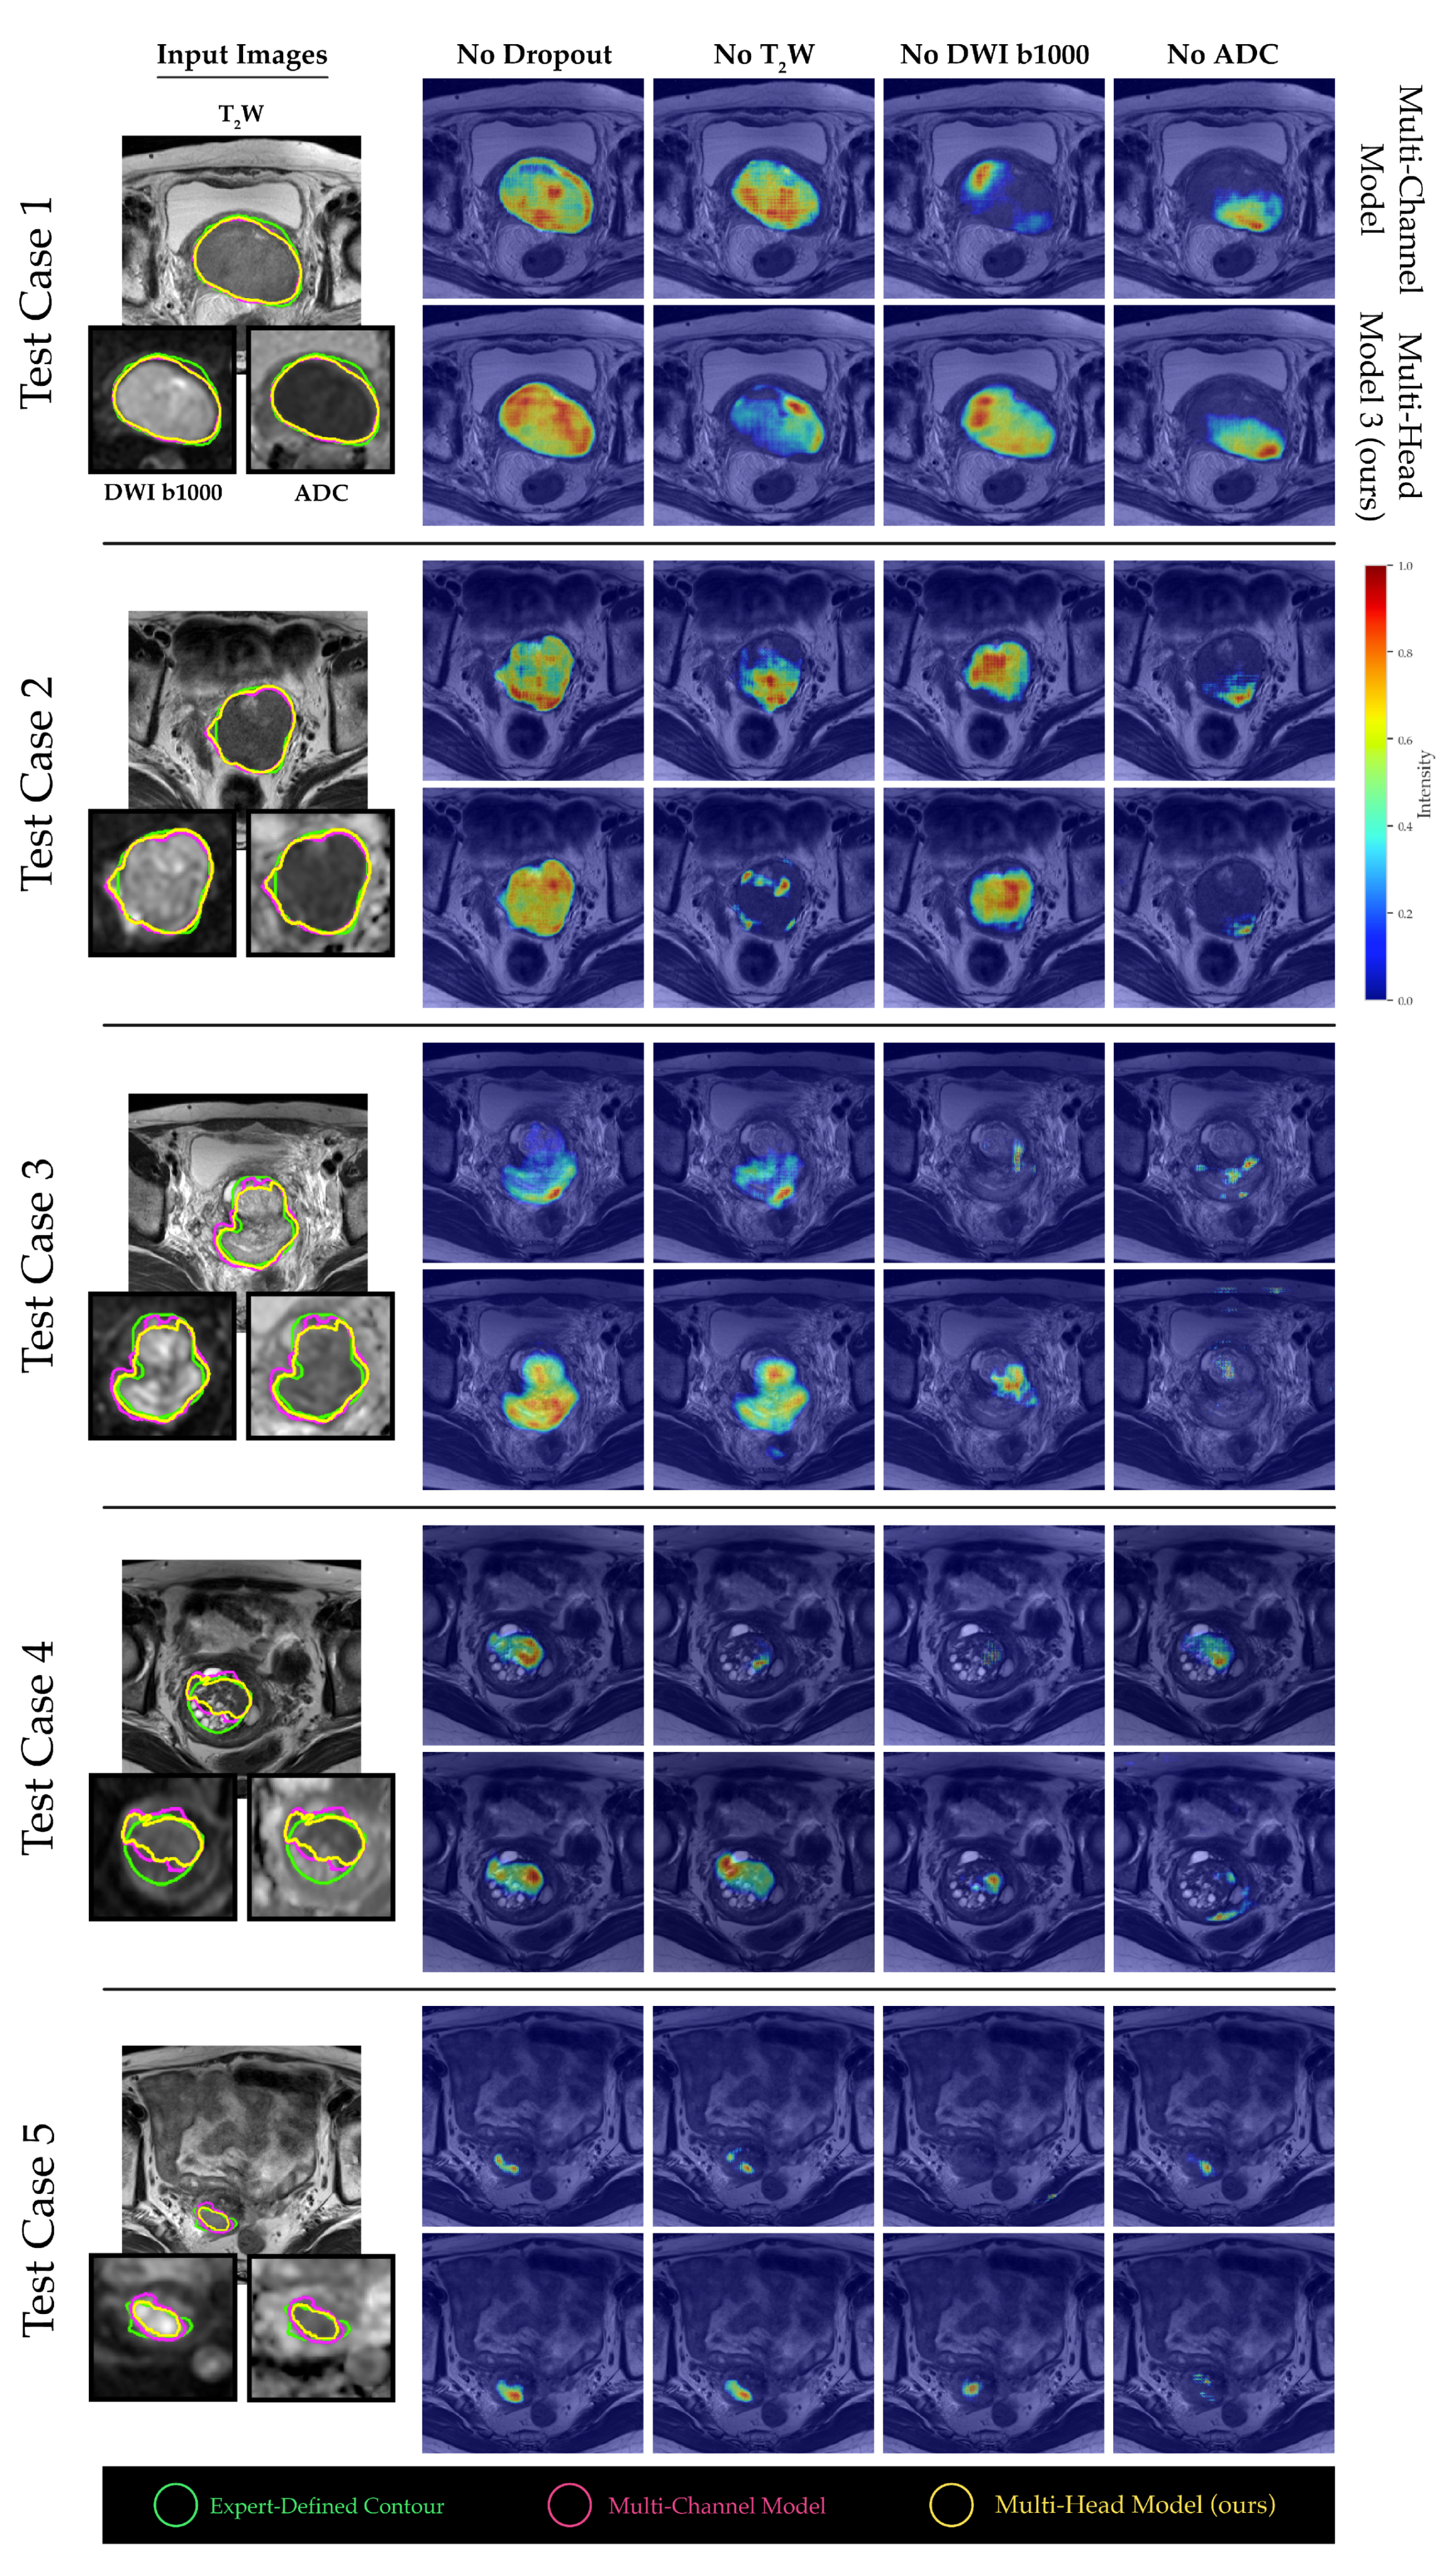

2.4. Channel Sensitivity Analysis and Visualization

3. Results